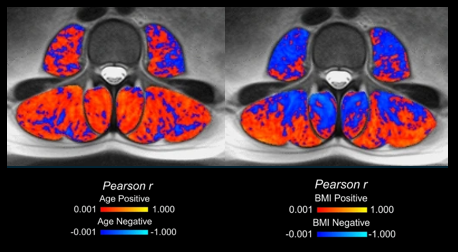

Three-dimensional spatial parametric mapping

Visualize and calculate the 3D spatial distribution of intramuscular fat in a standardized muscle template.